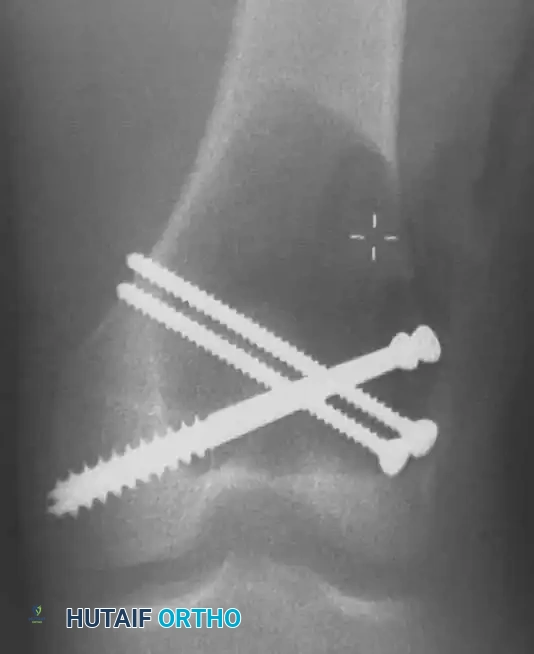

6. Structural Augmentation (Rebar Technique)

- Because the subchondral bone plate is often paper-thin following aggressive curettage, packing PMMA directly against it can lead to thermal injury to the articular cartilage or mechanical point-loading.

- To prevent this, structural cortical screws are placed across the cavity. These act as "rebar," distributing the mechanical load from the joint surface into the diaphyseal cortical bone.

Intraoperative photograph showing the placement of multiple structural screws within the cavity to support the subchondral plate and anchor the cement mantle.

Intraoperative fluoroscopy confirming the optimal trajectory and depth of the structural screws, ensuring they do not breach the articular surface.

7. Cementation (PMMA Application)

- The tourniquet is temporarily deflated to ensure hemostasis, then re-inflated. The cavity is thoroughly irrigated and dried.

- Standard viscosity PMMA bone cement is introduced into the cavity in a doughy state. It is digitally packed firmly around the screws and into all crevices of the burred cavity to ensure a perfect interdigitation with the host bone.

Postoperative Anteroposterior (AP) and Lateral radiographs demonstrating the final reconstruction. The radiopaque cement mantle and structural screws provide immediate stability.